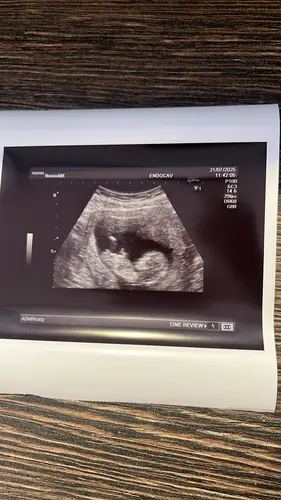

Ha! Ik ben 10+4 weken, is hier al iets op te zien? Ik snap niet zo goed hoe ik hiernaar moeten kijken. Wat denken jullie? 🥰